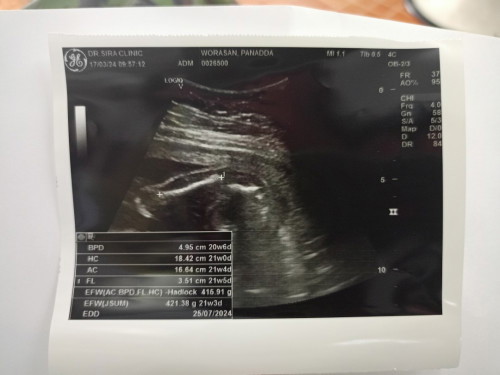

ซาวด์ดูเพศ อายุครรภ์ 21 w

ไปซาวด์ดูเพศ หมอบอกผู้หญิง 80 % มีโอกาสพลาดไหมค่ะ อายุครรภ์ 21 w 5 แม่ๆช่วยดูหน่อยค่ะ

80%ที่น่าจะเป็นไปได้ แต่ยังเหลือ20%ที่อาจเปรียนแปลงคะ